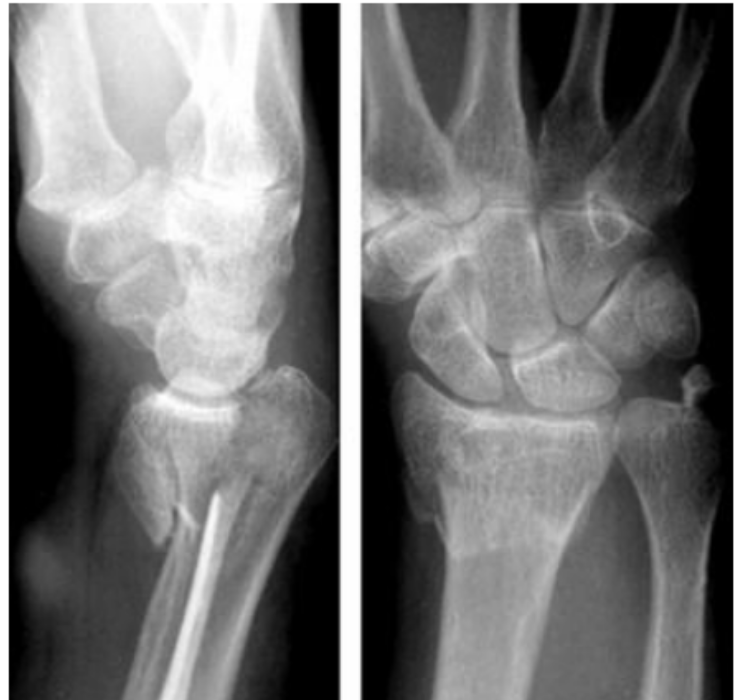

Que fractura se presenta en esta imagen

Colles

Inclinacion radial promedio

23° (13-30°)

Altura’longitud radial promedio

11mm

Inclunacion palmar/volar promedio

11° (11-14°)

En un paciente con una fractura con esta radiografia, que tratamiento se recomienda?

Clavillos + yeso, fijador externo o placas